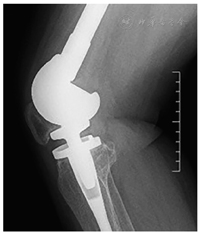

本组42例中共7例膝关节屈曲<90°,下蹲功能受限,其中2例出现行走功能受限并伴有疼痛。结合病史及影像学分析,7例患者中3例为肿瘤复发2次后行股骨假体置换的患者,2例为肿瘤复发1次后行股骨假体置换的患者,假体置换前均行刮除植骨内固定术。另2例患者因术后出现低位髌骨并发症(BPI=0.48),从而发生髌骨撞击导致疼痛行走功能受限(图6)。

关节功能为评价人工假体置换疗效的另一重要指标,本研究病例组中有7例患者出现膝关节屈伸功能受限(16.6%,7/42),从MSTS 93评分统计结果显示关节功能与手术次数、假体是否松动、是否翻修及截骨长度有关,手术次数增加导致软组织粘连加重影响关节功能。在本组病例中低位髌骨是导致膝关节功能受限的另一重要原因,通过测量BPI值,BPI<0.54为假性低位髌骨,为胫骨平台线抬高所致,此种情况多为医源性所致,而胫骨平台线抬高多为胫骨平台截骨量不够导致,这要求术者手术是胫骨平台截骨量应大致等于假体平台加聚乙烯垫的高度,从而避免医源性的低位髌骨。